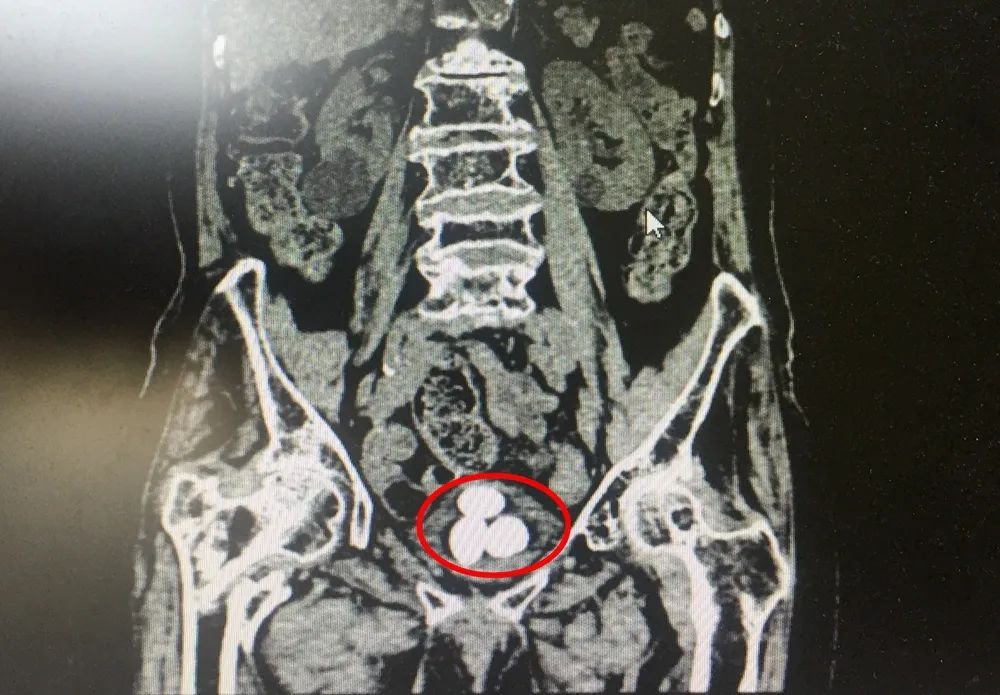

99歲的啟東老人楊奶奶,2年多前因?yàn)樗麑?dǎo)致了右側(cè)髖關(guān)節(jié)骨折,造成右腿畸形愈合,日常行走不便,長(zhǎng)期臥床。之后,老人開(kāi)始出現(xiàn)間斷血尿,到當(dāng)?shù)蒯t(yī)院檢查后發(fā)現(xiàn)患上了膀胱結(jié)石,因?yàn)闂钅棠棠挲g較大,手術(shù)風(fēng)險(xiǎn)高,醫(yī)生建議藥物治療,對(duì)癥消炎、止血。今年4月,楊奶奶再次出現(xiàn)了血尿情況,尿液深紅色,還有血塊。這一次,家人還是帶她去醫(yī)院保守治療,結(jié)果10多天了依然不見(jiàn)改善。持續(xù)的血尿,伴隨著尿頻、尿痛,讓老人的生活深受困擾。這樣的長(zhǎng)壽本是福氣,楊奶奶卻每日受著疾病煎熬,吃不下睡不著??粗赀~的母親痛苦難耐,楊奶奶的子女們也很揪心。到底還能不能做手術(shù)把結(jié)石取出來(lái)?帶著這樣的疑問(wèn),在住進(jìn)南通瑞慈醫(yī)院泌尿外科病房之前,子女們咨詢了多家醫(yī)院,卻都被婉言謝絕。▲影像資料顯示,楊奶奶的膀胱幾乎被三顆結(jié)石占滿

泌尿外科馬建國(guó)主任回憶老人病情時(shí)說(shuō),楊奶奶長(zhǎng)期臥床,結(jié)石越長(zhǎng)越大。入院后的檢查結(jié)果顯示,老人的膀胱內(nèi)長(zhǎng)了三顆結(jié)石,最大的直徑達(dá)到4厘米,有鴿子蛋那么大,膀胱基本上被結(jié)石占滿了。據(jù)馬主任介紹,膀胱結(jié)石目前多采用鈥激光微創(chuàng)碎石手術(shù),手術(shù)本身并不復(fù)雜,但楊奶奶已是99歲高齡,心、腦、肺功能都不是太好,基礎(chǔ)情況不容樂(lè)觀,無(wú)論是術(shù)中的麻醉風(fēng)險(xiǎn)、發(fā)生心腦血管意外風(fēng)險(xiǎn),還是術(shù)后出現(xiàn)并發(fā)癥的風(fēng)險(xiǎn),都比普通病人高出了一大截。“高齡不是絕對(duì)的手術(shù)禁忌。如果繼續(xù)采取保守治療,老人未來(lái)的日子勢(shì)必沒(méi)有生活質(zhì)量可言。想讓她安享晚年,首先得想辦法幫她把這三顆頑石取出。風(fēng)險(xiǎn)是不可避免的,家屬也非常支持我們的工作。因此我們做了充分的術(shù)前準(zhǔn)備,組織多學(xué)科會(huì)診,評(píng)估手術(shù)耐受情況,完善檢查排除手術(shù)禁忌,又經(jīng)過(guò)一段時(shí)間調(diào)養(yǎng),幫助她改善心肺功能?!?/section>手術(shù)過(guò)程中還有一段小插曲,通常該類結(jié)石手術(shù)需要采取“截石位”,雙腿叉開(kāi)抬高,類似于女性順產(chǎn)的姿勢(shì)。而老人因?yàn)橛彝然?,只能采取左腿抬高的“半截石位”手術(shù),增加了手術(shù)操作難度。憑借著多年的手術(shù)經(jīng)驗(yàn)和過(guò)硬的技術(shù),馬建國(guó)主任順利為楊奶奶完成了手術(shù)。